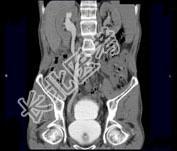

- 多项选择题男,53岁, 无痛性血尿2个月余,CT扫描如图示, 下列说法正确的是 ( )

A、右侧输尿管下段可见沿输尿管走行的软组织肿块影

B、软组织肿块边缘毛糙不平

C、其上方的输尿管扩张

D、考虑为输尿管移行细胞癌

E、考虑为输尿管内血块